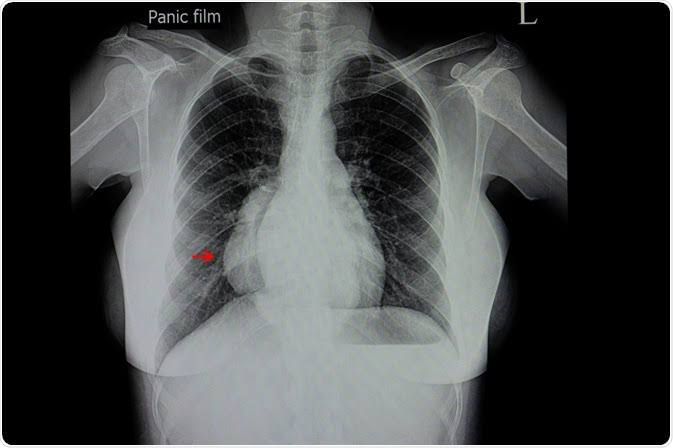

Management of mediastinitis

Antibiotics are given to treat infection. Sometimes surgery is needed to drain infected fluid from the chest, to repair the tear in the esophagus, or both. There is no treatment for fibrosing mediastinitis.